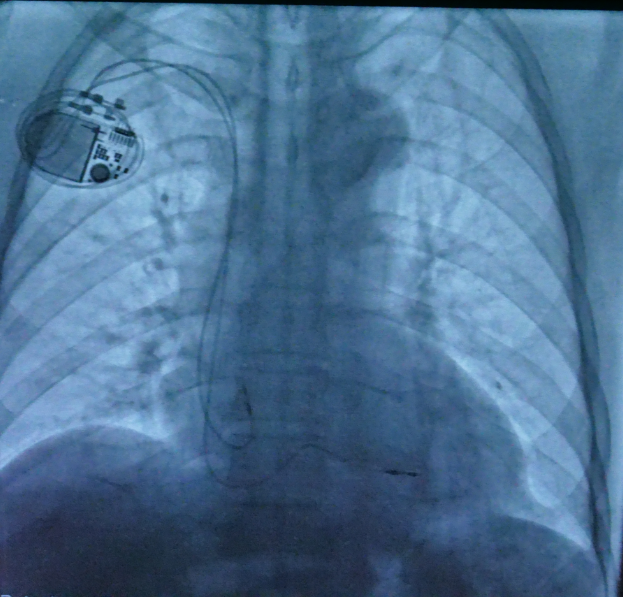

该患者为82岁男性,腰椎手术后,有核磁检查需求,同时体型偏瘦,更小更薄的起搏器可减少并发症发生的可能性,提高植入设备后的生活质量。此外,患者高龄,需使用长寿命起搏器以减少更换次数,避免更换起搏器导致感染等并发症的风险。综合考虑后,科室为患者选择了一款新型抗核磁双腔起搏器,其寿命长达10年,体积仅为10毫升。

心内科副主任医师何榕、刘元伟在科主任张萍的指导下完成手术,用时50分钟,手术过程十分顺利,术后患者无任何不适。囊袋制作细致加上起搏器本身体积小,术后外观几乎察觉不到起搏器的存在,不但减少了囊袋磨损的可能,还保持了美观的效果。

既往的抗核磁起搏器使用寿命不够长,需更换次数较多;而长寿命起搏器又不能做核磁共振检查。因此,清华长庚心内科引入新型抗核磁长寿命双腔起搏器,完美解决这部分患者的需求。该起搏器厚度仅为6mm,体积10cc,预估寿命可达到10年以上;可接受在1.5T磁场强度下的全身核磁扫描;同时具有长时间记录腔内图以及做出心衰预警等功能。